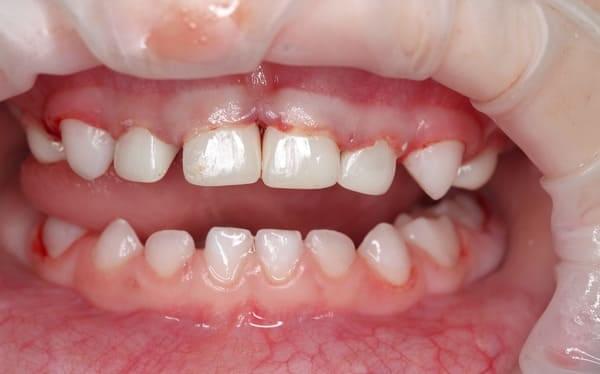

Дівчинка 2 років, але зуби вже мають глибокі ураження із залученням у запальний процес пульпи (“нерва”) зуба. На жаль, так трапляється і зволікати в такому випадку не можна. Було проведено лікування в умовах анестезіологічного забезпечення під контролем досвідченої анестезіологічної команди. Передні зубчики відновлено естетичними коронками, на жувальних зубчиках проведена герметизація фісур, а один вже має глибоке ураження карієсом, тому теж покритий коронкою. Одразу після лікування ясна можуть виглядати дещо травмованими, але за кілька днів вони повністю відновляться.